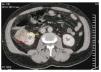

Cuenta como antecedente de importancia: hipertensión de 15 años de evolución en tratamiento con enalapril una tableta cada 8 horas, además de exposición crónica a productos del antimonio inhalado por su trabajo como soldador ahora ya pensionado, como factores de riesgo6,7, niega alguna otra enfermedad crónica, pérdida de peso ponderal o síntomas constitucionales, refiere nunca haber fumado. Se realiza entonces tomografía computada (TC) abdominopélvica simple y contrastada, encontrando tumor renal heterogéneo de 50 x 45.9 mm, invadiendo desde cáliz medio hasta espacio cortical, la cual tiene realce periférico de medio de contraste (figs. 2 y 3), sin evidencia de metástasis torácica o local, vejiga sin lesiones ocupantes. Se realiza además pruebas de laboratorio complementaria reportando Hb: 12.6 g, Hto: 35.6%, plaquetas: 142,000, leucos: 8.4, glucosa: 120 mg, urea: 53 mg, creatinina: 1.04 mg, tiempos de sangrado y pruebas funcionales hepáticas dentro de parámetros normales. Uroanálisis: leucocitos 0 por campo, eritrocitos 0 por campo, bacterias proteínas y nitritos negativo.

Figura 2. Corte topográfico donde se muestra una lesión sólida de 4.5 x 5.0 cm, en su borde externo del riñón derecho con densidad heterogéneo.

Características tomográficas de la lesión: como se ha descrito anteriormente, los tumores renales de células claras se desarrollan del túbulo contorneado proximal, mientras que los de conductos de Bellini tendrán su origen de los túbulos colectores, por lo que serán emergidos de la médula del riñón. No existen hallazgos específicos que puedan diferenciar un tumor renal de células claras contra uno de túbulos colectores, sólo que éstos se encontrarán más hacia la médula, tendrán una presentación poco más heterogénea, se involucrarán mayormente en el seno renal, con crecimiento infiltrativo preservando el contorno renal, así como eventuales imágenes quísticas pequeñas dentro de la misma lesión9.